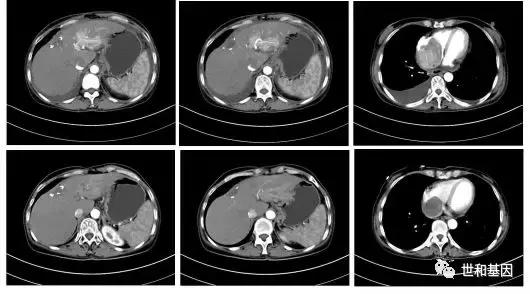

- 2019年3-7月,“帕博利珠单抗 200mgd1+多西他赛120mgd1+卡铂450mgd2”方案化疗6周期。2周期后复查CT评估病情进展(PD),但患者一般情况明显好转,肿瘤标志物明显下降,继续原方案治疗。4周期后复查CT病灶明显缩小。

治疗前后CT变化